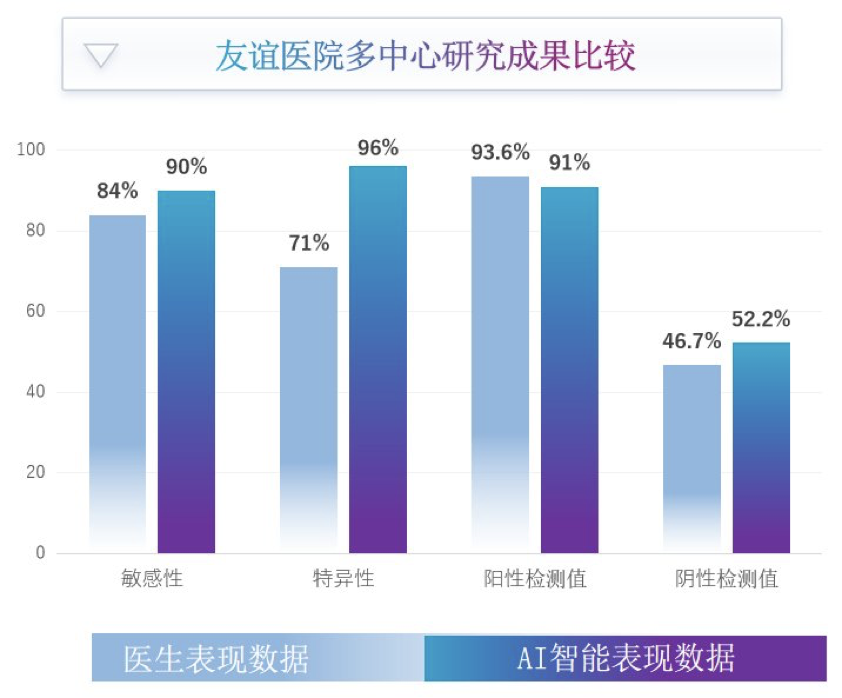

这种方法的诊断精度和质量跟比较资深的医生差不多,比那些经验较少的年轻医生还要更准确一些。在人机协同方面,我们的算法产品提供了一些诊断结果,允许医生做出 double check,这种方法的效果一般来说是优于医生自己用肉眼做判断,因此诊断质量也有所提升。

另一方面,医院的成本降低、收入增加。之前医院可能需要 10 台或者 20 台工作站,并且每台都比较贵,可能需要 20-30 万,现在可以替换为一台中央服务器,以私有云的方式在医院部署起来,运行我们的 AI 产品,使用算法的服务,每个医生用一台普通电脑只需要几千块钱的成本连到服务器,就可以完成跟之前一样的事情,医生的工作时间减少,工作质量上升,医院的收入增加。右边的图是一个对比,即不同类型三甲医院、基层医院在使用冠脉 CTA 产品前后收入的变化,收入有显著的上升,因为诊断的病人增多了。